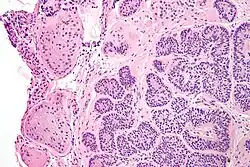

Micrograph of a Sertoli cell nodule. H&E stain. -

Sertoli cell nodules are unencapsulated nodules that consist of:[2][3][4]

- cells arranged in well-formed tubules (that vaguely resemble immature Sertoli cells), with

- bland hyperchromatic oval/round nuclei that are stratified, and

- may contain eosinophilic (hyaline) blob in lumen (centre).